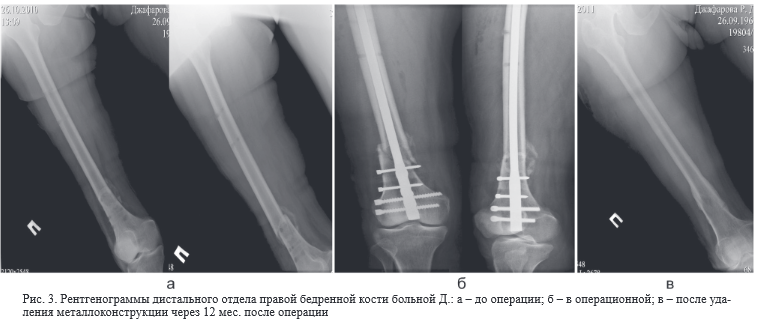

Смещение дистального отдела

Смещение дистального отдела 104 фото